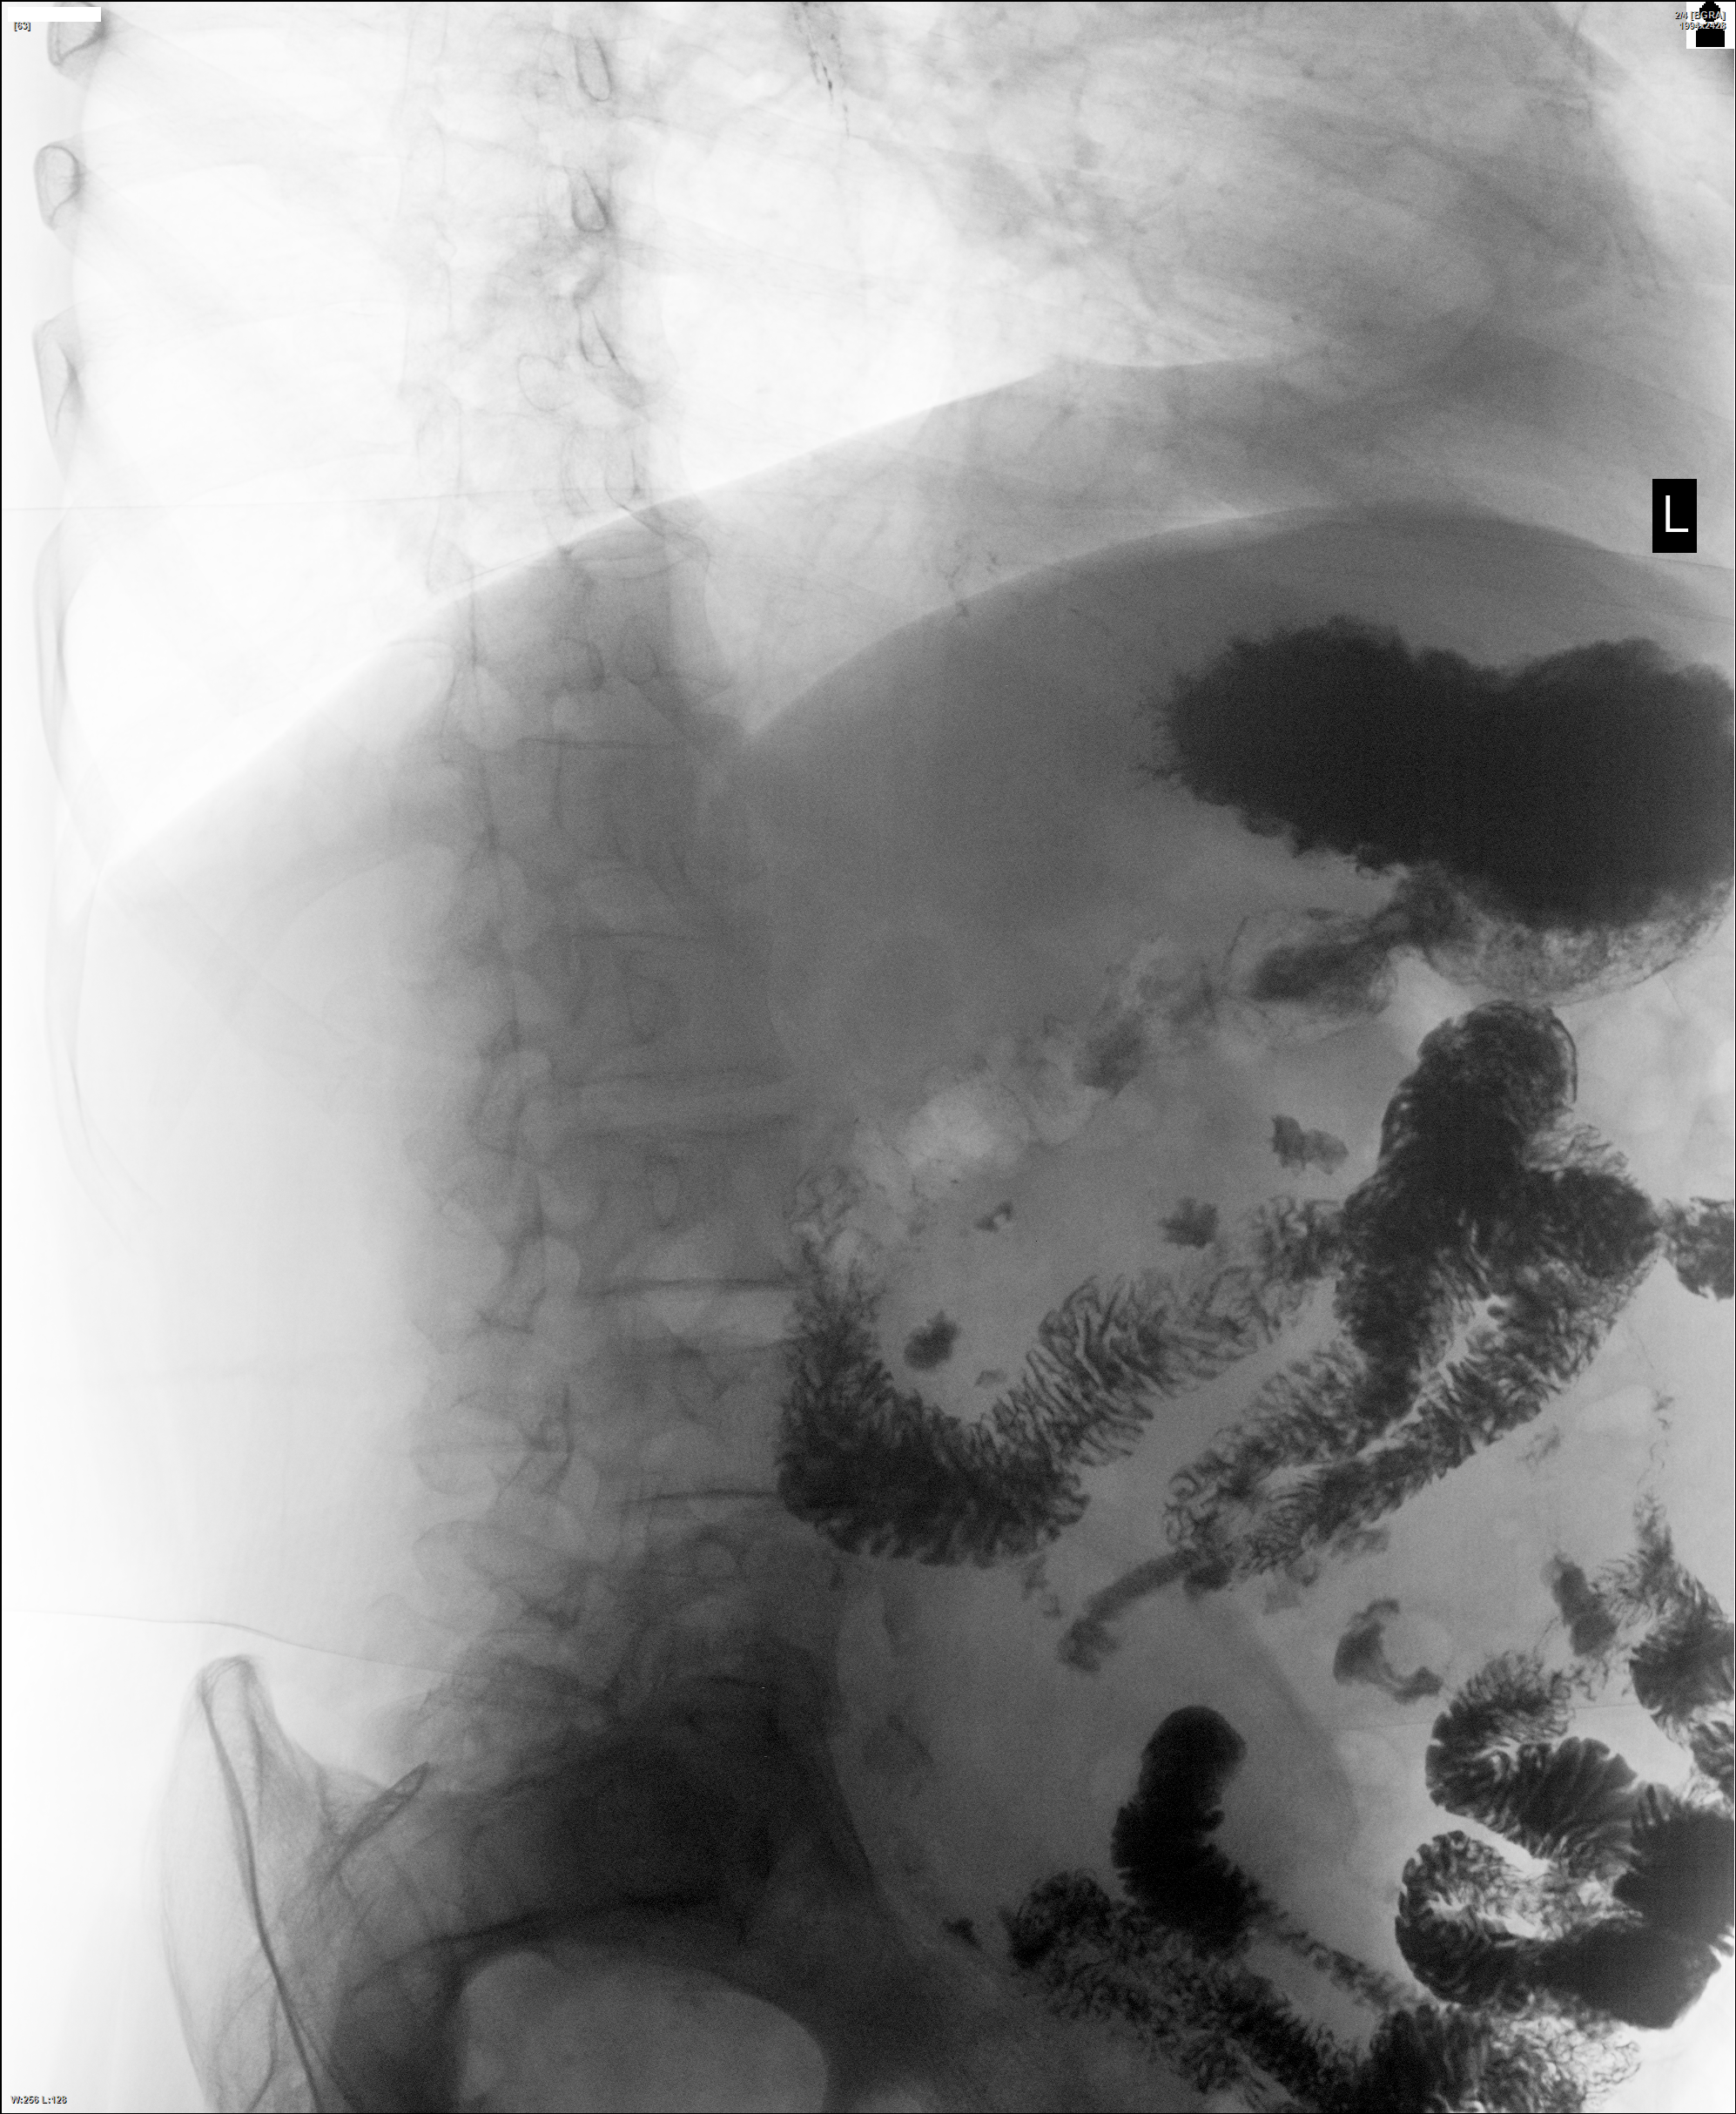

Мужчина 63 лет. Мучает изжога уже несколько лет. Много снимков было сделано лёжа, но барий был не слишком густой - характерной грыжевой картины сразу не увидал. Признаки есть, конечно, не спорю. Случай представил, чтобы показать, что на грыжу лучше барий сметанкой давать.) Снова снимки не маркировал. Но надеюсь, учтёте, где пациента лёжа снимал.)

Грыжа есть. Она плохо контрастирована.

Насчёт оптимальной проекции. Для меня грыжа вполне убедительна во многих проекциях. Были разные у нас учителя. Здесь, кстати, она слегка скользящая. Если бы чётче немного законтрастировал, снимки бы Вам подарил - для приложения к приведённой странице с интересной цитатой "фиксированная, что скользит!"))

Пожалуйста! На снимке одном обзначил. Но присмотритесь к складкам на первом из серии - желудочные видны уже и там. А главное, что послужило основой для самопроверки - угол Гиса увеличенем насторожил и маленький газовый пузырь, он же - свод желудка.

Косвенные признаки я указал те, что были видны стоя, не на животе. А лёжа, во всех проекциях - косых, на спине и на животе, видны складки желудочные, просто бария мало оказалось этой грыже.) Фиксация есть, но смещаема слегка она. Потому и решил Вам в коллекцию снимки передать - цитата интересна, хоть и странна!)